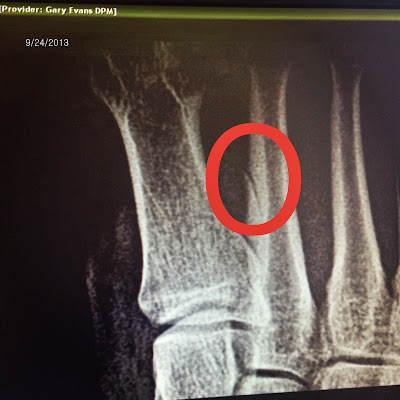

Toe fracture stress 2nd metatarsal doctor visit ray second mai addiction running serious base shows near. Mai running addiction: 2nd toe metatarsal stress fracture: 2nd doctor visit

Toe fracture stress 2nd metatarsal doctor visit ray second mai addiction running serious base shows near. Sesamoid bone